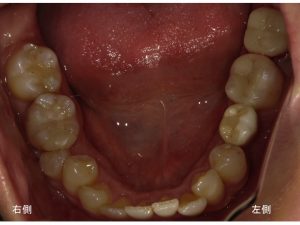

次に下顎です。

下顎左側奥2歯に金属治療が行ってあります。